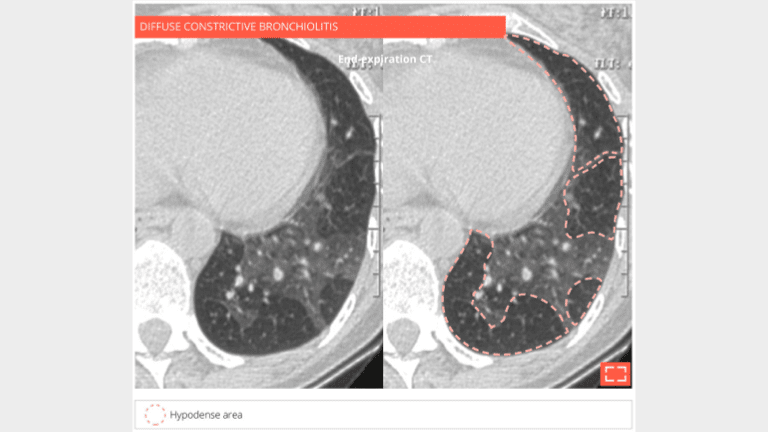

Diffuse constrictive bronchiolitis in a bone marrow transplant patient.

End-expiratory CT scan: the lung has a patchy heterogeneous mosaic attenuation alternating between normal dense areas and hypodense areas suggesting expiratory air trapping, revealing small airways disease consistent with the diagnosis of constrictive bronchiolitis.